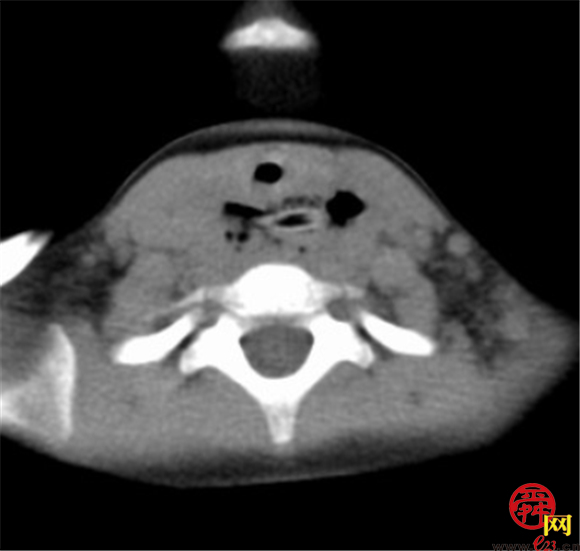

颈部及胸部CT:C6/7水平脊柱前方见条状中空高密度影,大小约19.6*5.0*6.9mm,周围软组织肿胀,向上延伸至咽后间隙,向下至上纵隔区,组织间隙显示模糊,可见散在多发点、片状气体密度影,以高密度影周围为著,相应区域气管受压前移,部分管腔显示较窄。